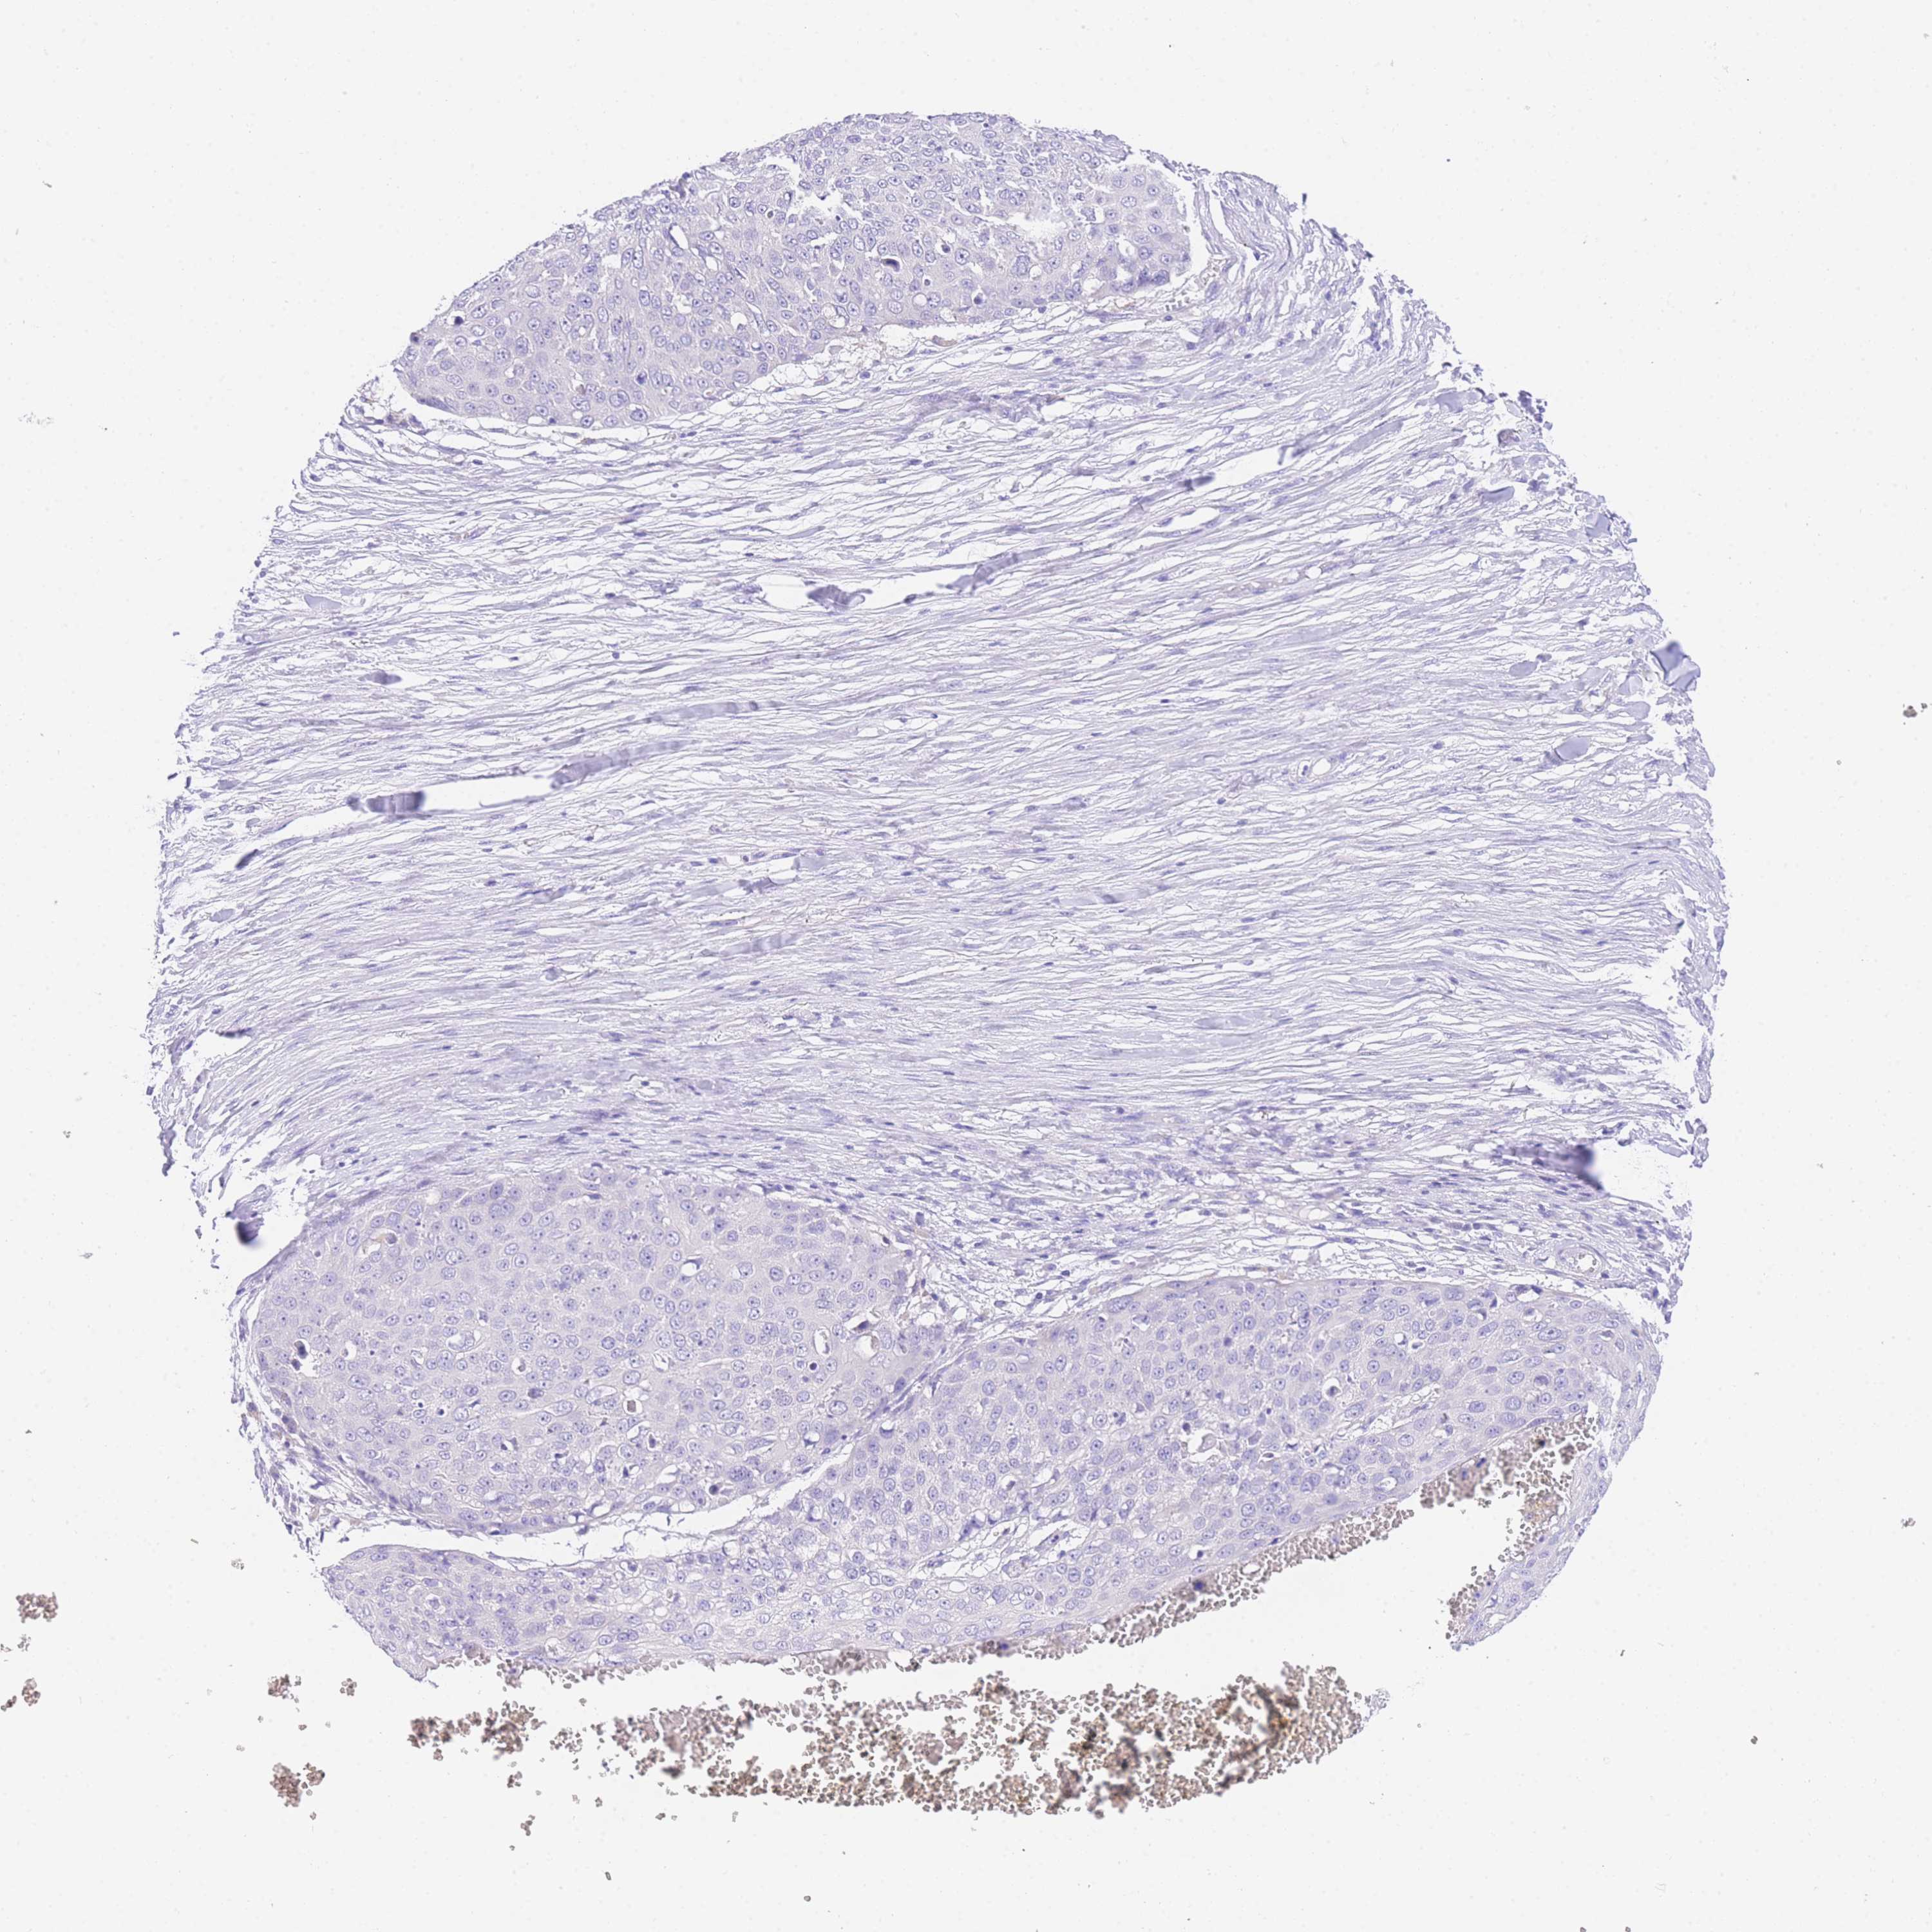

Basal cell and squamous cell cancer

SKIN CANCER - Protein expressioni

A mouse-over function shows sample information and annotation data. Click on an image to view it in a full screen mode. Samples can be filtered based on level of antibody staining by selecting one or several of the following categories: high, medium, low and not detected. The assay and annotation is described here.

Each image is clickable and will lead to virtual microscopy that enables deeper exploration of all samples and also displays staining intensity scores, fraction scores and subcellular localization as well as patient and tissue information for each sample.

Antibody HPA049809

Basal cell carcinoma

Squamous cell carcinoma, NOS

Squamous cell carcinoma, metastatic, NOS